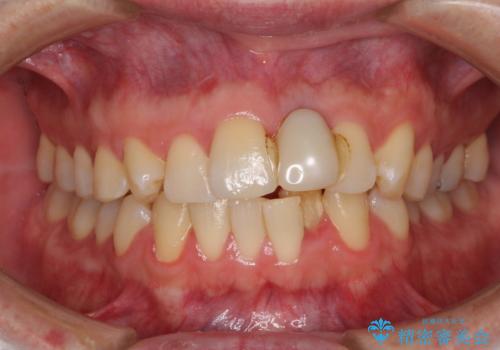

インプラントが唇側に埋入されており、セラミッククラウンの歯肉ラインが左右非対称となっていました。

仮歯は両サイドの歯と接着剤で止められており、接着が著しく変色していたため、セラミッククラウンが装着されて自然な口元となりました。